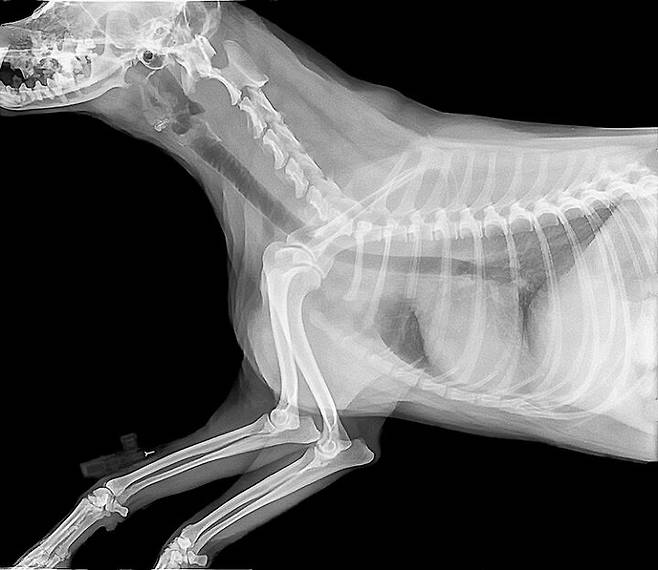

성견의 경우 체중 1kg당 하루에 242mg을 섭취해야 하고 강아지는 이보다 2배 더 섭취해야 합니다. 칼슘이 개의 치아와 뼈를 튼튼하게 하는 영양소라는 것은 누구나 알고 있는 사실입니다. 자라고 있는 반려견의 사료에 칼슘이 부족하면 뼈가 약해지는 구루병이 생기고 다른 기관에도 치명타를 입힐 수 있으며, 칼슘이 너무 많으면 골 기형의 원인이 됩니다.

칼슘은 뼈에 99%가 저장되어 있고 나머지 1%는 혈액 등에 흩어져 있습니다. 비록 혈액 속에 있는 칼슘은 극소량이기는 하지만 혈액을 따라 몸속을 돌면서 세포의 기능을 유지시켜주고 세포의 분열에도 관여합니다. 게다가 칼슘은 심장과 뇌의 활동과 호르몬 분비에 중요한 역할을 합니다. 칼슘 농도의균형이 깨지면 뼈뿐만 아니라 심장이나 뇌에도 기능장애가 올 수 있습니다.